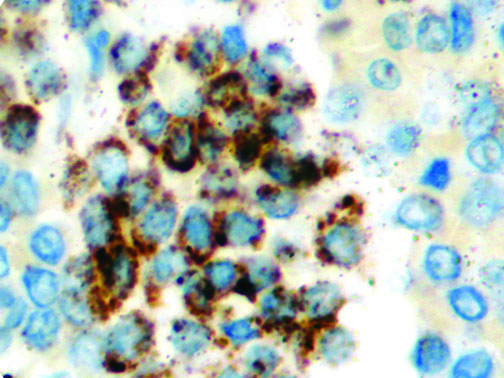

It is the ICU physician who is most likely to witness one of the deadliest manifestations of the abnormal immunological response, the cytokine storm syndrome (CSS). This response is also referred to by some as the cytokine release syndrome (CRS). CSS is characterized by continuous activation and expansion of macrophage and lymphocyte populations, which secrete large amounts of cytokines, causing the cytokine storm. This massive cytokine release is akin to hemophagocytic lymphohistiocytosis (HLH) disease, a syndrome characterized by initial unchecked and persistent activation of cytotoxic T lymphocytes and NK cells.

Clinical and laboratory manifestations of HLH include fever, enlarged liver and/or spleen, neurologic dysfunction, coagulopathy, liver dysfunction, cytopenias (i.e., low levels of erythrocytes, leukocytes, and/or platelets), hypertriglyceridemia, hyperferritinemia, hemophagocytosis, and eventually diminished NK cell activity as the immune system becomes progressively paralyzed. HLH can be familial (primary HLH) or secondary to another disease process (sHLH), such as rheumatic disease, in which it is referred to as macrophage activation syndrome (MAS, characterized by elevated ferritin).